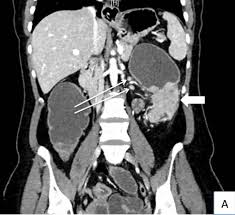

Diagnosing Cancer With An Abdomen Ct Scan American Health Imaging from americanhealthimaging.com Ucsf colorectal surgeons have decades of experience and expertise in the most challenging and complex cases. Can a pet scan detect colon polyps? Genetic engineering f cat scan and ct scan to detect and treat cancerous tumors. A ct scan can help doctors find cancer and show things like a tumor's shape and size. In many cases, the stage of your cancer may not be fully determined until after colon cancer surgery. Answers from hundreds of doctors about benign to serious symptoms. Cat scans and carcinoid tumors can be very scary. Can ct scan detect colon cancer?

Ct scanners first began to be installed in 1974. If you have colon cancer, would a ct scan show it? Ucsf colorectal surgeons have decades of experience and expertise in the most challenging and complex cases. Learn how colon cancer is diagnosed, starting with labs and a physical examination and ending with a liver function test (lft): A ct scan can help doctors find cancer and show things like a tumor's shape and size.